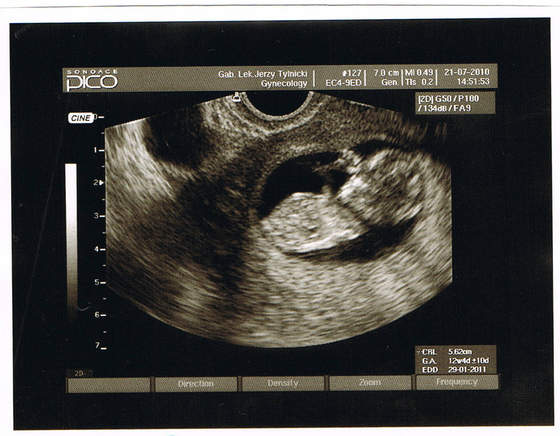

zaraz spróbuje a ty skarbie kiedy masz wizyte ??

Mi wychodziło jak miałam 5t5d że jestem w 7 a to awykonalne było a na następnym usg okazało się że jednak jest prawidłowo przeze mnie liczone